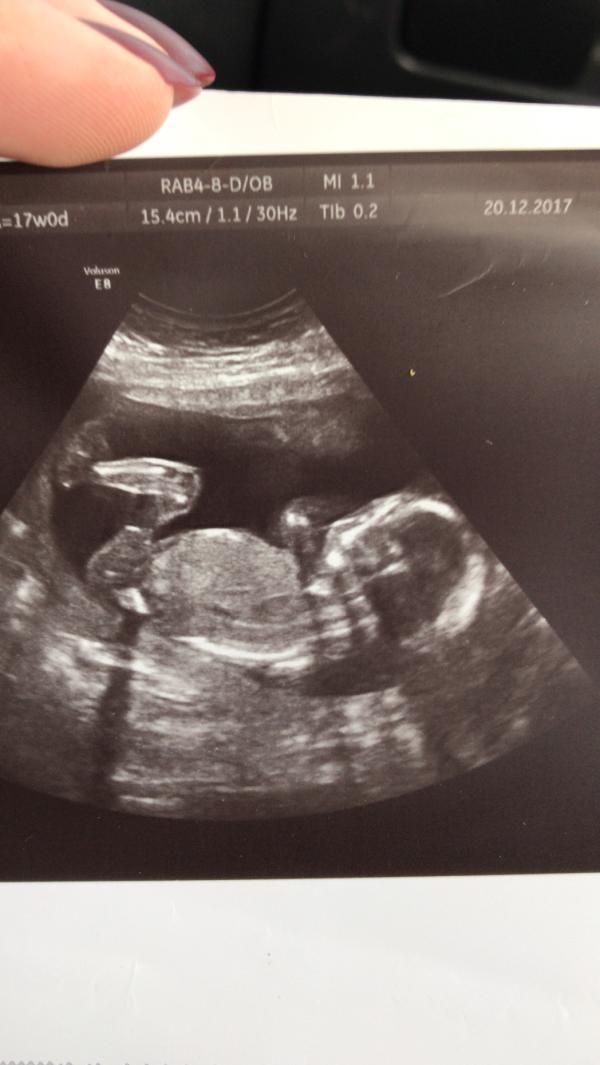

Не выдержала, пошла узнавать пол☺️ как же сильно отличается платное узи: показали, рассказали, покрутили) на первом УЗИ в конце картину показали и все. А здесь и фотографию сделала) и узнала, что будет хулиган😂 девчонки а вам любопытно было, кто у вас?))) делали дополнительно УЗИ или по плану все было?)